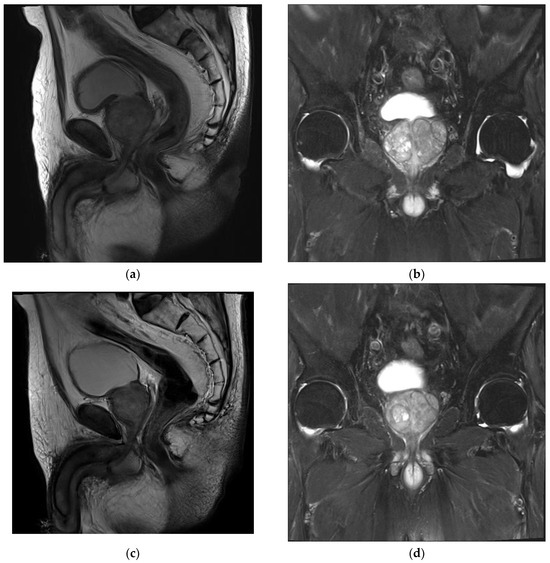

3. Results